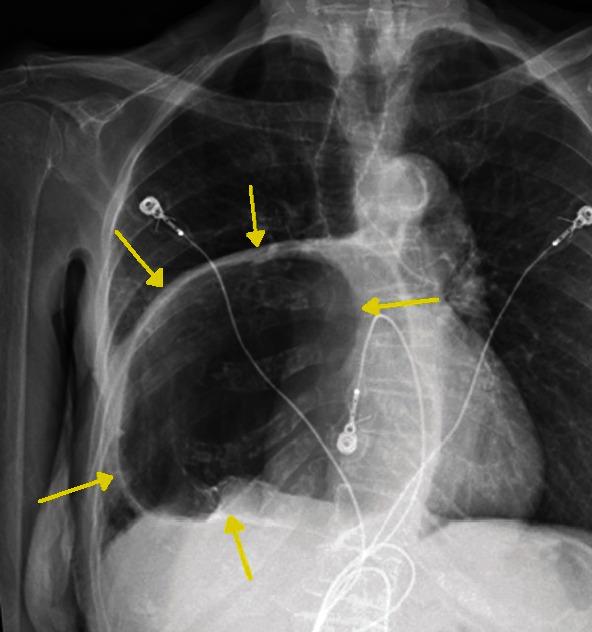

Hiatal hernia is a not uncommon anatomic disorder resulting in portions of the bowel occupying space in the thoracic cavity. There are a number of antecedent risk factors including obesity but not hiatal hernias resulting in symptoms. When symptoms do occur, they can include chest pain, nausea, abdominal pain, and gastroesophageal reflux. Cardiac arrhythmias have also been reported as associated conditions resulting from a hiatal hernia. To date, however, a complete heart block secondary to a hiatal hernia has not been reported. An 88-year-old female with a history of GERD (gastroesophageal reflux disease) was found to have a large hiatal hernia at endoscopy after she presented to the emergency department with nausea and abdominal pain. Prior to her scheduled surgical repair, she developed symptomatic third degree heart block which resolved with nasogastric tube deflation of the gastric contents. After surgical repair of the hiatal hernia, she developed episodes of atrial fibrillation with rapid ventricular response and was started on diltiazem. She eventually converted back to normal sinus rhythm and remained dysrhythmia free. In addition to other known arrhythmias associated with hiatal hernia, a complete heart block can also be seen. Acute management requires deflation of the chest occupying hernia. This appears to be the one of the first reported cases of complete heart block caused by hiatal hernia.

食管裂孔疝是一种较为常见的解剖学疾病,可导致部分肠管占据胸腔空间。有许多相关危险因素,包括肥胖,但食管裂孔疝并不一定会引发症状。当出现症状时,可能包括胸痛、恶心、腹痛和胃食管反流。心律失常也被报道为食管裂孔疝的相关病症。然而,迄今为止,尚未有因食管裂孔疝导致完全性心脏传导阻滞的报道。一名88岁有胃食管反流病病史的女性,因恶心和腹痛到急诊科就诊,在内镜检查时发现有巨大食管裂孔疝。在预定进行手术修复之前,她出现了有症状的三度心脏传导阻滞,通过鼻胃管排出胃内容物后得以缓解。食管裂孔疝手术修复后,她出现了伴有快速心室反应的房颤发作,并开始使用地尔硫䓬治疗。她最终恢复为正常窦性心律,且未再出现心律失常。除了与食管裂孔疝相关的其他已知心律失常外,还可见到完全性心脏传导阻滞。急性处理需要使占据胸腔的疝内容物排空。这似乎是首例报道的由食管裂孔疝引起的完全性心脏传导阻滞病例。